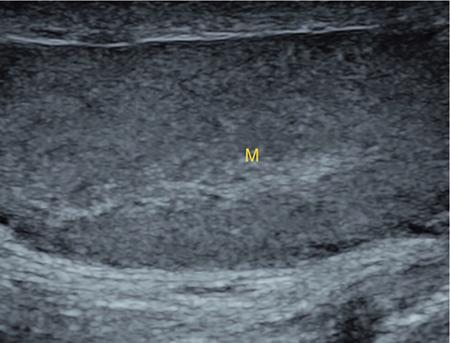

IMAGING ANATOMY OF MALE REPRODUCTIVE SYSTEM Ganesh Rajagopal The male reproductive system is formed by testes, ejaculatory ducts, seminal vesicles (SVs), prostate and penis. Various diagnostic imaging modalities like ultrasound (US), computed tomography (CT), magnetic resonance imaging (MRI) and positron emission tomography (PET) are helpful in the diagnostic evaluation of male reproductive system. Various indications for imaging may include acute scrotum (testicular torsion, trauma and epididymo-orchitis), scrotal swelling (hydrocele, spermatocele, idiopathic scrotal wall oedema and scrotal abscess) and infertility. US and MRI are the commonly used imaging modalities in male reproductive system which complement each other. CT is not very useful due to poor contrast resolution. Ultrasound imaging (US) with a high-frequency linear (7.5–10 MHz) transducer probe has become the imaging modality of choice for scrotal evaluation. Scrotal US is an excellent imaging modality as it can demonstrate abnormalities in testis as well as in paratesticular structures. Scrotal wall is formed by the skin, superficial fascia, dartos muscle, the external spermatic fascia, cremasteric fascia and the internal spermatic fascia. The scrotum is divided into two cavities by a median raphe. This multilayered scrotal wall is poorly delineated in US and MRI, it is typically hypointense on both T1- and T2-weighted images. Testes are paired organs, located normally in scrotal sac, suspended by the spermatic cords. Each testis is examined in orthogonal transverse and longitudinal planes, with both grey scale and colour Doppler modes, to assess its volume and blood flow. Volume of testis is calculated by length × height × width × 0.71. A total volume (both testes) of >30 mL and a single testicular volume of 12–15 mL is generally considered normal for adults. Testes are supplied by the testicular arteries, which arise from the aorta and enter the spermatic cord at deep inguinal ring to reach the upper pole of testis. Pampiniform plexus of veins surrounds the testis and appears as a serpiginous tubular structure posterior to it, measuring >2–3 mm in diameter. Testes are oval shaped, with homogeneous echotexture on grey scale US. Along with the epididymis, they are surrounded by an echogenic capsule, known as the tunica albuginea. Tunica albuginea is covered by tunica vaginalis, which is a remnant of the processus vaginalis and both represent closed sac of peritoneum with two layers. This tunica albuginea is seen extending into posteromedial testis and form the mediastinum testis (Fig. 11.2.1.1), which consists of ducts, nerves and blood vessels. The mediastinum testis is seen as a thin echogenic band. Rete testis is formed by the convergence of seminiferous tubules, seen as a hypoechoic area adjacent to mediastinum testes. The epididymis is a comma-shaped, elongated structure placed at the posterior border of the testis, which drains the efferent ductules (Fig. 11.2.1.2). It has head, body and tail. The head overlies the superior pole of the testis and is isoechoic or slightly hyperechoic whereas, the body and tail are located behind and along the inferior pole and are usually isoechoic. The tail of the epididymis continues into vas deferens (VD), which along with the nerves, lymphatic and vascular structures, forms the spermatic cord (Fig. 11.2.1.3). The spermatic cord appears as an echogenic band in the inguinal canal. The normal adult testis is a homogeneous oval structure that appears hyperintense on T2-weighted sequences and hypointense–isointense on T1-weighted images (Fig. 11.2.1.4). The tunica which surrounds the testis is hypointense T1- and T2-weighted sequences. Epididymis is isointense on T1-weighted images but hypointense on T2-weighted images compared to testis (Fig. 11.2.1.5). Both testicles and epididymis enhance after intravenous administration of gadolinium (Gd) MR contrast agents. Prostate, though visualized by transabdominal scan is better assessed by transrectal high frequency (7.5–10 MHz) ultrasound transducer (TRUS) with patient in left lateral decubitus position. The prostate gland is divided into the anterior fibromuscular stroma (devoid of glandular tissue), transition zone, central zone, periurethral zone and peripheral zone. The base of the prostate is located superiorly and contiguous with the bladder neck whereas, the apex of the prostate is located at the inferior aspect continuous with the striated muscles of the urethral sphincter. The neurovascular bundle is seen to course near the posterolateral aspect of prostate, which is a preferential route of tumour spread. The prostate appears as a cone-shaped organ and shows uniform low echogenicity (Fig. 11.2.1.6). The outer gland (central and peripheral zones) is generally more echogenic than the inner gland. The transition and central zones of the prostate have similar MR signal intensity and cannot be differentiated, hence, are collectively referred as the central gland. On T2-weighted MR images, the normal peripheral zone is homogeneously hyperintense, whereas the central gland tissue is typically hypointense or isointense compared to the skeletal muscle (Fig. 11.2.1.7). The capsule and the anterior fibromuscular stroma appear hypointense on T2-weighted MR images. The SVs are seen as septate tubular cystic structures, appearing uniformly anechoic in US, above the prostate with distal portion of VD is seen medial to it. The duct of SV and VD joins to form the ejaculatory duct, which drains into the prostatic urethra via verumontanum. SVs show ‘bow-tie’ appearance in transversal scans, and a club or tennis-racket shape in longitudinal scans (Fig. 11.2.1.8). On MR, SVs are seen as elongated fluid-containing structures with thin septa, which is hypointense on T1 and hyperintense on T2-weighted MR images (Fig. 11.2.1.9). The VD is seen as a tubular structure with low signal intensity in both T1- and T2-weighted images, on either side. The dilated distal portion of VD (ampulla), appears hyperintense on T2-weighted images, similar to that of the SV due to the fluid content (Fig. 11.2.1.10). The penis, being a superficial organ, is usually examined with US, although MRI is reserved as problem solving modality. The penile body contains two paired muscles – corpora cavernosa and a corpus spongiosum. The former performs as a main erectile body while the latter contains the penile urethra (Fig. 11.2.1.11). Dartos fascia forms the outer layer and the Buck fascia forms the inner layer, which contain the deep dorsal vein (DDV) and a paired dorsal neurovascular bundle. The corpus spongiosum and corpora cavernosa are of high signal intensities on T2-weighted MR images and intermediate-low signals on T1-weighted MR images. The tunica albuginea being a fibrous sheath, surrounds all the three muscles, is hypointense on all sequences (Fig. 11.2.1.12). IMAGING ANATOMY OF FEMALE REPRODUCTIVE SYSTEM Saranya The female reproductive system comprises of uterus, cervix, fallopian tubes, ovaries, vagina and vulva. Ultrasonography (transabdominal and transvaginal) is the primary imaging modality of choice for imaging the female pelvis. Computed tomography (CT) is less often used for pelvic imaging. It provides a quick and systematic overview with coverage of the abdomen in the same session. Hence, CT is well suited for staging pelvic cancers and for imaging gynaecologic and nongynaecologic diseases presenting with acute abdominal pain. Pelvic anatomy is well demonstrated by magnetic resonance imaging (MRI). The contrast resolution of T2-weighted images form the basis for superb tissue characterization of MRI. Uterus is a thick-walled fibromuscular organ composed of myometrium and endometrium. It has two major divisions, namely, the body (corpus) and cervix. The fundus lies above the ostia of fallopian tubes. The normal uterus measures between 5 and 9 cm in length and is in an anteverted position, in relation to the urinary bladder. The myometrium shows three layers on USG, a compacted thin, hypoechoic inner layer forms subendometrial halo, a thicker, homogenously echogenic middle layer and a thinner, hypoechoic outer layer (peripheral to arcuate vessels). The appearance of the endometrium varies with the phase of the menstrual cycle. It appears as a thin echogenic line early in the proliferative phase and shows hypoechoic thickening (4–8 mm) as proliferative phase progresses. It shows a triple layer (sandwich or trilaminar) appearance in the mid cycle and may measure up to 12–16 mm. During secretory phase after ovulation, the layers are seen hyperechoic due to the increasing complexity of glandular structure and secretions (Fig. 11.2.2.1). Postmenopausally, the endometrium decreases in thickness. Endometrial thickness of 5 mm is taken as cut-off. Women on hormonal therapy acceptable endometrial thickness is up to 8 mm. Three-dimensional US permits multiple views to be reconstructed from a single sweep through the uterus. Sonohysterogram is the study of choice for detailed evaluation of the endometrial cavity pathologies. The cervix begins at the inferior narrowing of the uterus (isthmus) at the internal os, which is identified by the entrance of uterine vessels. It has supravaginal and vaginal portions. It is 3–4 cm long and shortens after childbirth. In premenarche women, cervix is larger than corpus, forming approximately 2/3 of the uterine mass. During menarche, there is preferential growth of the corpus and in nulliparous women, corpus and cervix are roughly equal, whereas in parous woman, corpus forms approximately 2/3 of the uterine mass. Uterus is an extraperitoneal organ. The peritoneum extends over urinary bladder dome to anterior uterus, forming anterior cul-de-sac (vesicouterine pouch) and posteriorly, the peritoneum extends more inferiorly to the upper portion of vagina, forming the posterior cul-de-sac (pouch of Douglas, rectouterine pouch), which forms the most dependent portion of the female pelvis. Supporting ligaments of the uterus comprise mainly of broad ligaments, which extend laterally to the pelvic wall and round ligaments, which arise from uterine cornu near fallopian tubes to course anteriorly, pass through the inguinal canal to insert on the labia majora. Connective tissue thickening at the base of the broad ligament forms the uterosacral ligaments posteriorly, cardinal ligaments laterally and vesicouterine ligaments anteriorly. CT examination displays the uterus as a triangular or ovoid soft tissue structure behind the urinary bladder (Fig. 11.2.2.2). Following the administration of intravenous contrast, there is enhancement of myometrium that helps to delineate the endometrium. The vagina, cervix and corpus can be differentiated by morphological characteristics and enhancement pattern. The uterine corpus is typically triangular, whereas cervix is more rounded. The vagina has an appearance of flat rectangle at the level of fornix. The broad ligament and round ligaments are seen coursing laterally and anteriorly, respectively. The main source of vascular supply to uterus is from the uterine arteries. The uterine arteries pass within the broad ligament to enter the uterus, adjacent to the lateral fornices. The uterine artery passes over the ureter at the level of the cervix. Then it courses superiorly, along the lateral margin of the uterus and anastomoses with the ovarian artery. Uterine arteries give rise to arcuate arteries, which run in the outer third of myometrium. Radial arteries extend through the myometrium, which terminate as spiral arteries in the endometrium. The venous system parallels the arterial system, forms a complex venous network in the parametrium and drains to the iliac veins. Middle and lower thirds of the uterus are drained by obturator, parametrial and paracervical lymph nodes. Lymphatic drainage from the upper corpus and fundus goes to the common iliac and paraaortic lymph nodes. MRI provides a more comprehensive view of the uterine anatomy. On MRI, the uterus and cervix show uniform low to intermediate signal on T1-weighted images. On T2-weighted images, uterus shows three distinct zones, namely high signal endometrium, low signal junctional zone and intermediate signal myometrium (Fig. 11.2.2.3). The normal thickness of the junctional zone varies from 2 to 8 mm. A thickness of 9 to 12 mm is equivocal and greater than 12 mm is abnormal. Both endometrium and junctional zone become thin with oral contraceptive intake. Endometrial atrophies and the junctional zone is absent in postmenopausal women. The endocervical canal shows high signal on T2-weighted images, whereas cervical stroma shows low signal, contiguous with the junctional zone. An outer layer of intermediate signal smooth muscle is present. Nabothian cysts representing obstructed, mucous secreting glands are commonly seen as low signal on T1-weighted images and high signal on T2-weighted images. Parametrium shows low to intermediate signal intensity on T1-weighted images and variable signal intensity on T2-weighted images. The round ligaments and uterosacral ligaments show low signal intensity, cardinal ligaments and associated venous plexuses show high signal intensity on T2-weighted images. Ovaries are located posterolateral to the body of the uterus between the uterus and the pelvic sidewall. The internal iliac vessels lie immediately posterior to the ovary. Exact position is variable due to the laxity in the ligaments, parity, uterine size and position. On USG, medulla of the ovaries is mildly hyperechoic compared to the hypoechoic cortex. Developing follicles appear anechoic (Fig. 11.2.2.4). Corpus luteum may have a thick, echogenic ring and haemorrhage is common.